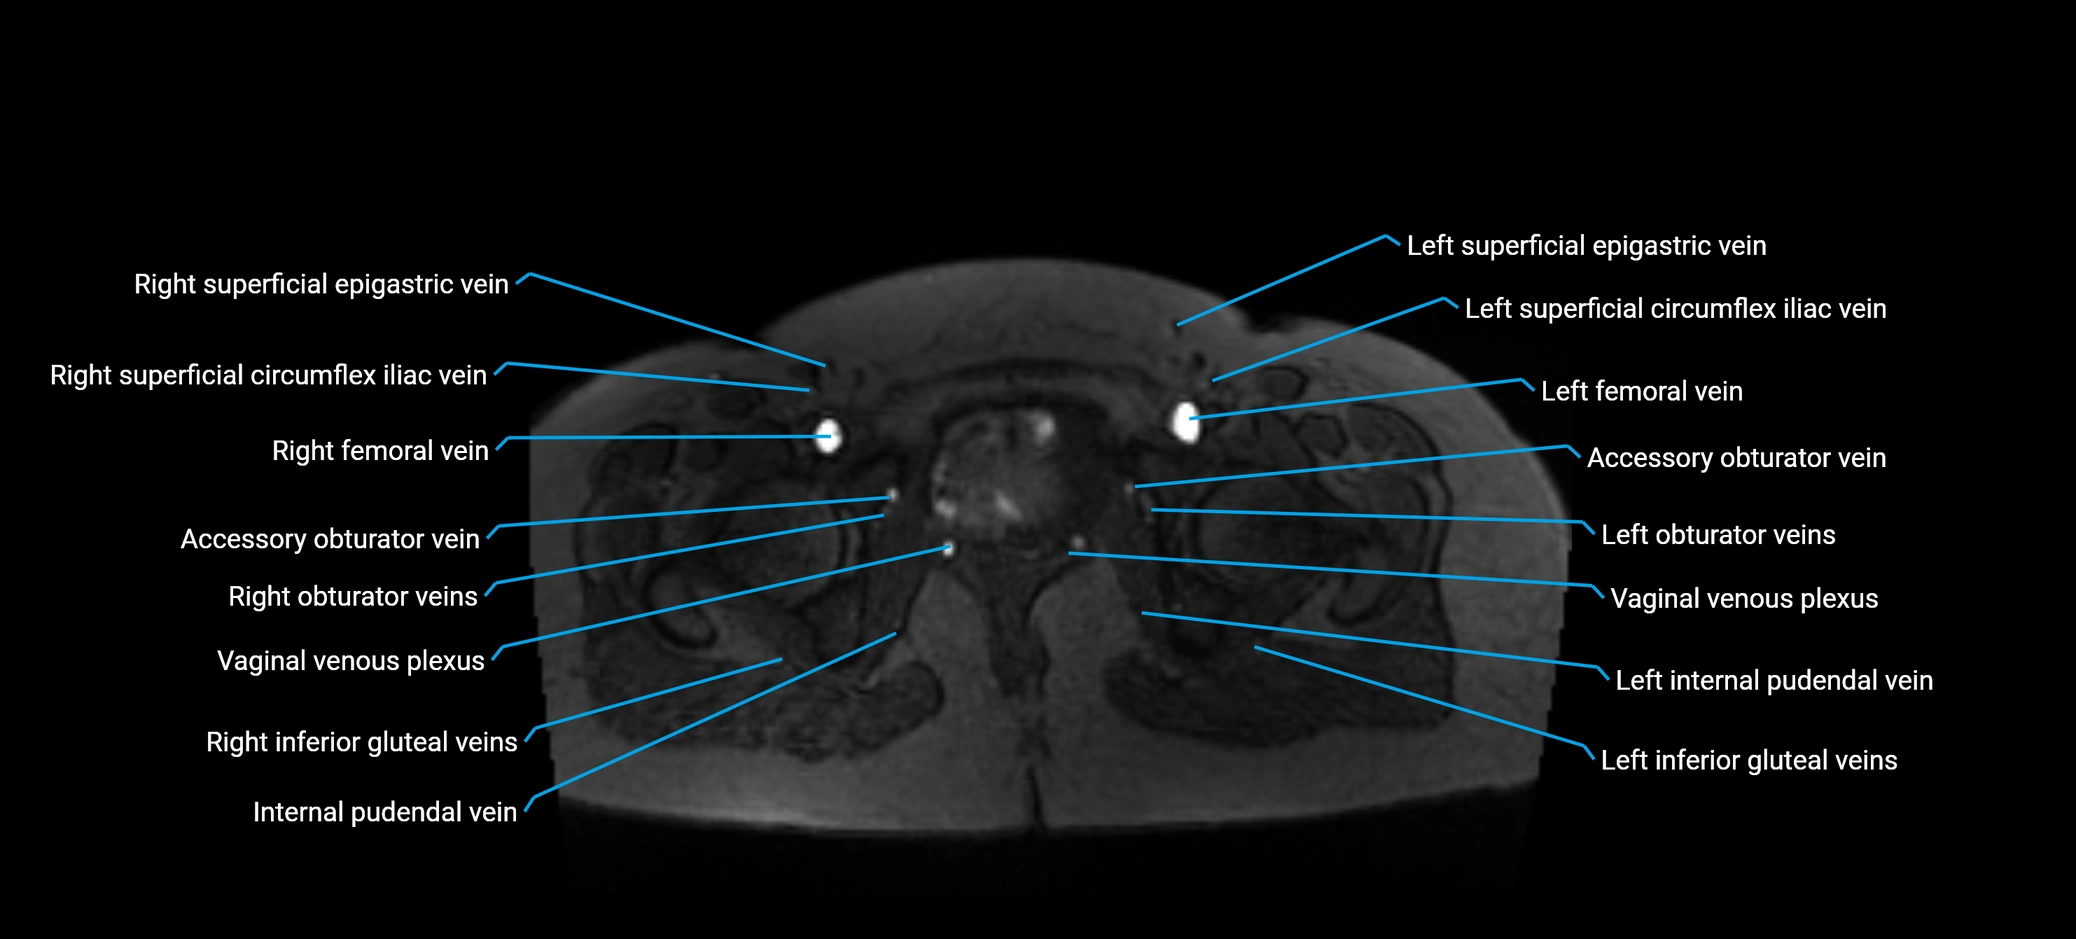

MRI image

image